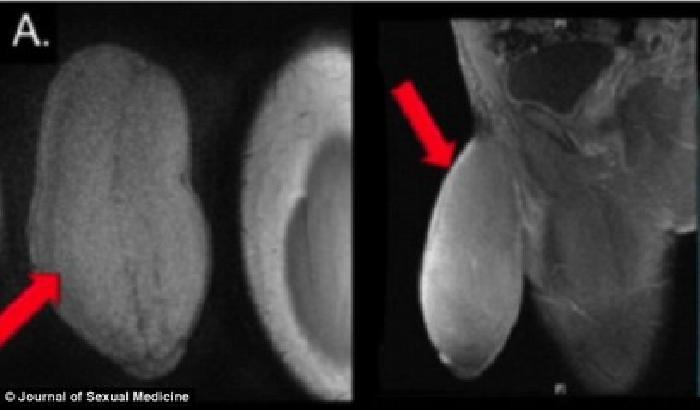

La cosa ancora più drammatica è il fatto che il brasiliano è nato con una deformazione al collo così grave che la sua testa rimane sospesa all’ingiù dietro le spalle.